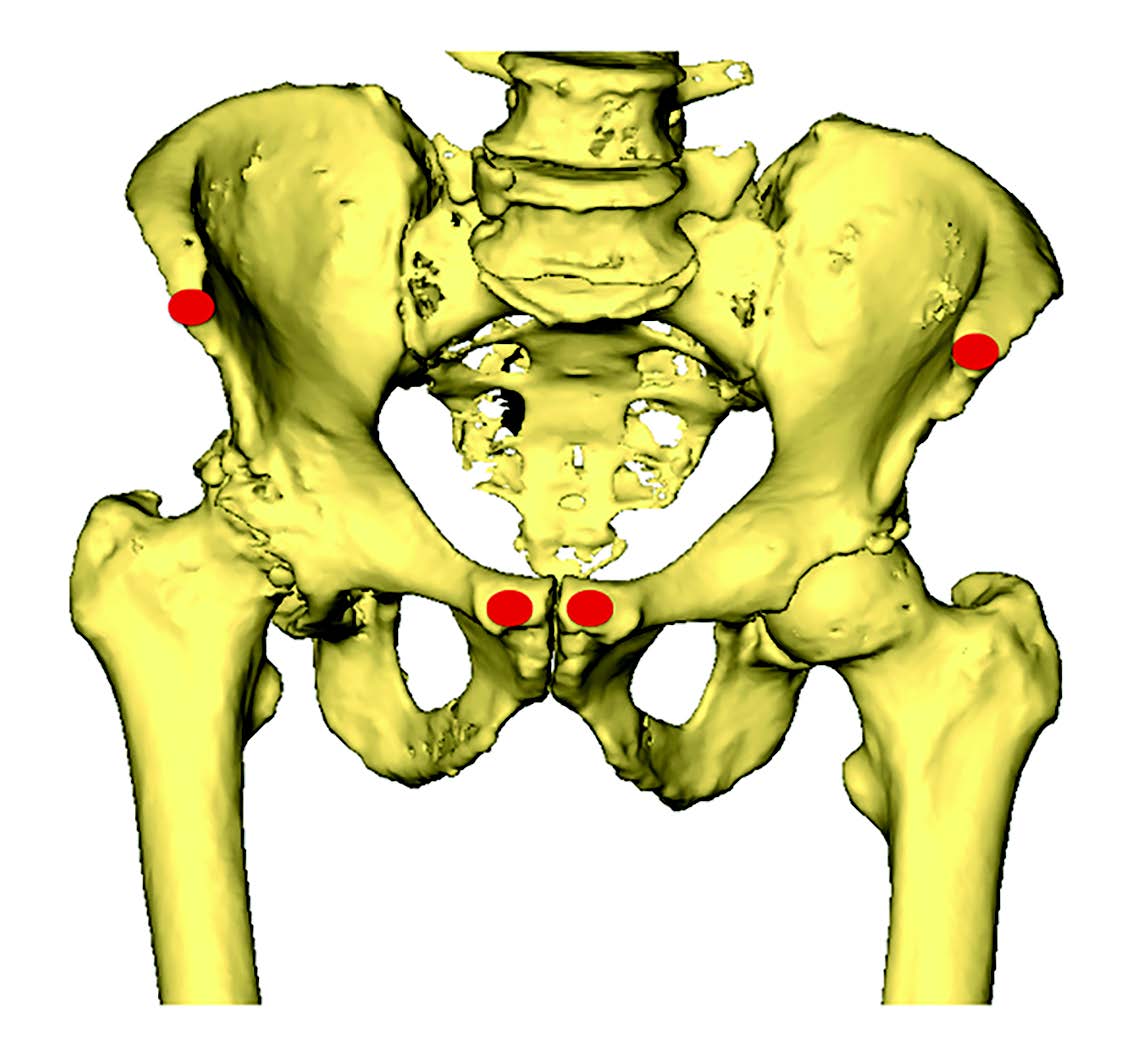

CT-based preoperative planning was used for 392 records out of 472 arthroplasties performed from 2008 to 2014. Standard x-ray is still used for elderly patients and for second side surgery. The software makes it possible to use several types of implants, including a 129° self-locking straight stem. I now always use this stem when I can, the 129° angle corresponding to the mean value of a CT database (Fig. 1).

Step 1: The frontal and side on scout view can be used to perform length measurements outside and within the joint (Fig. 2).

Step 3: The position of the pelvis uses the Lewinnek plan (reference plane based on the anterior superior iliac spines and the pubic symphysis). It is calculated automatically by the software. It can be used to quantify acetabular inclination and anteversion (Fig. 3).

Step 5: femur position: the software measures the posterior bicondylar line then defines a femur from the front and side on (Fig. 5). The greater trochanter, the digital fossa and the lesser trochanter landmarks can thus be specified. All of these measures are used to define the femoral torsion and offset.